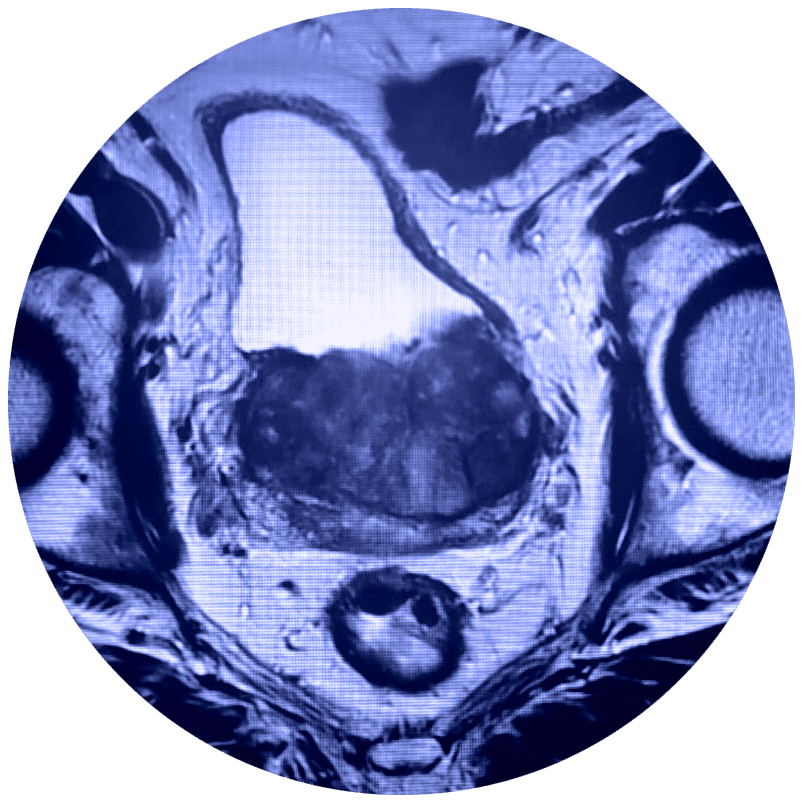

El estudio de Resonancia Multiparamétrica de Próstata no requiere de exposición a la radiación, evalúa el movimiento de las moléculas de agua (denominado difusión del agua) y el flujo sanguíneo (denominado imágenes de perfusión) adentro de la próstata. Esto ayuda al médico a diferenciar entre el tejido enfermo y el tejido sano de la próstata.

En estudio de Resonancia Multiparamétrica de Próstata tiene una sensibilidad diagnóstica de aproximadamente el 85% en los diferentes tipos de cáncer de próstata, especialmente aquellos que son significativamente agresivos. Además, cuenta con imágenes de alta resolución para lesiones o tumores pequeños.

El médico utiliza la RMN para evaluar el cáncer de próstata y ver si se encuentra confinado a la próstata. La Mp-MRI proporciona información acerca de las moléculas de agua y del flujo sanguíneo a través de la próstata. Esto ayuda a determinar si el cáncer se encuentra presente y, si es el caso, si es agresivo y si se ha diseminado.